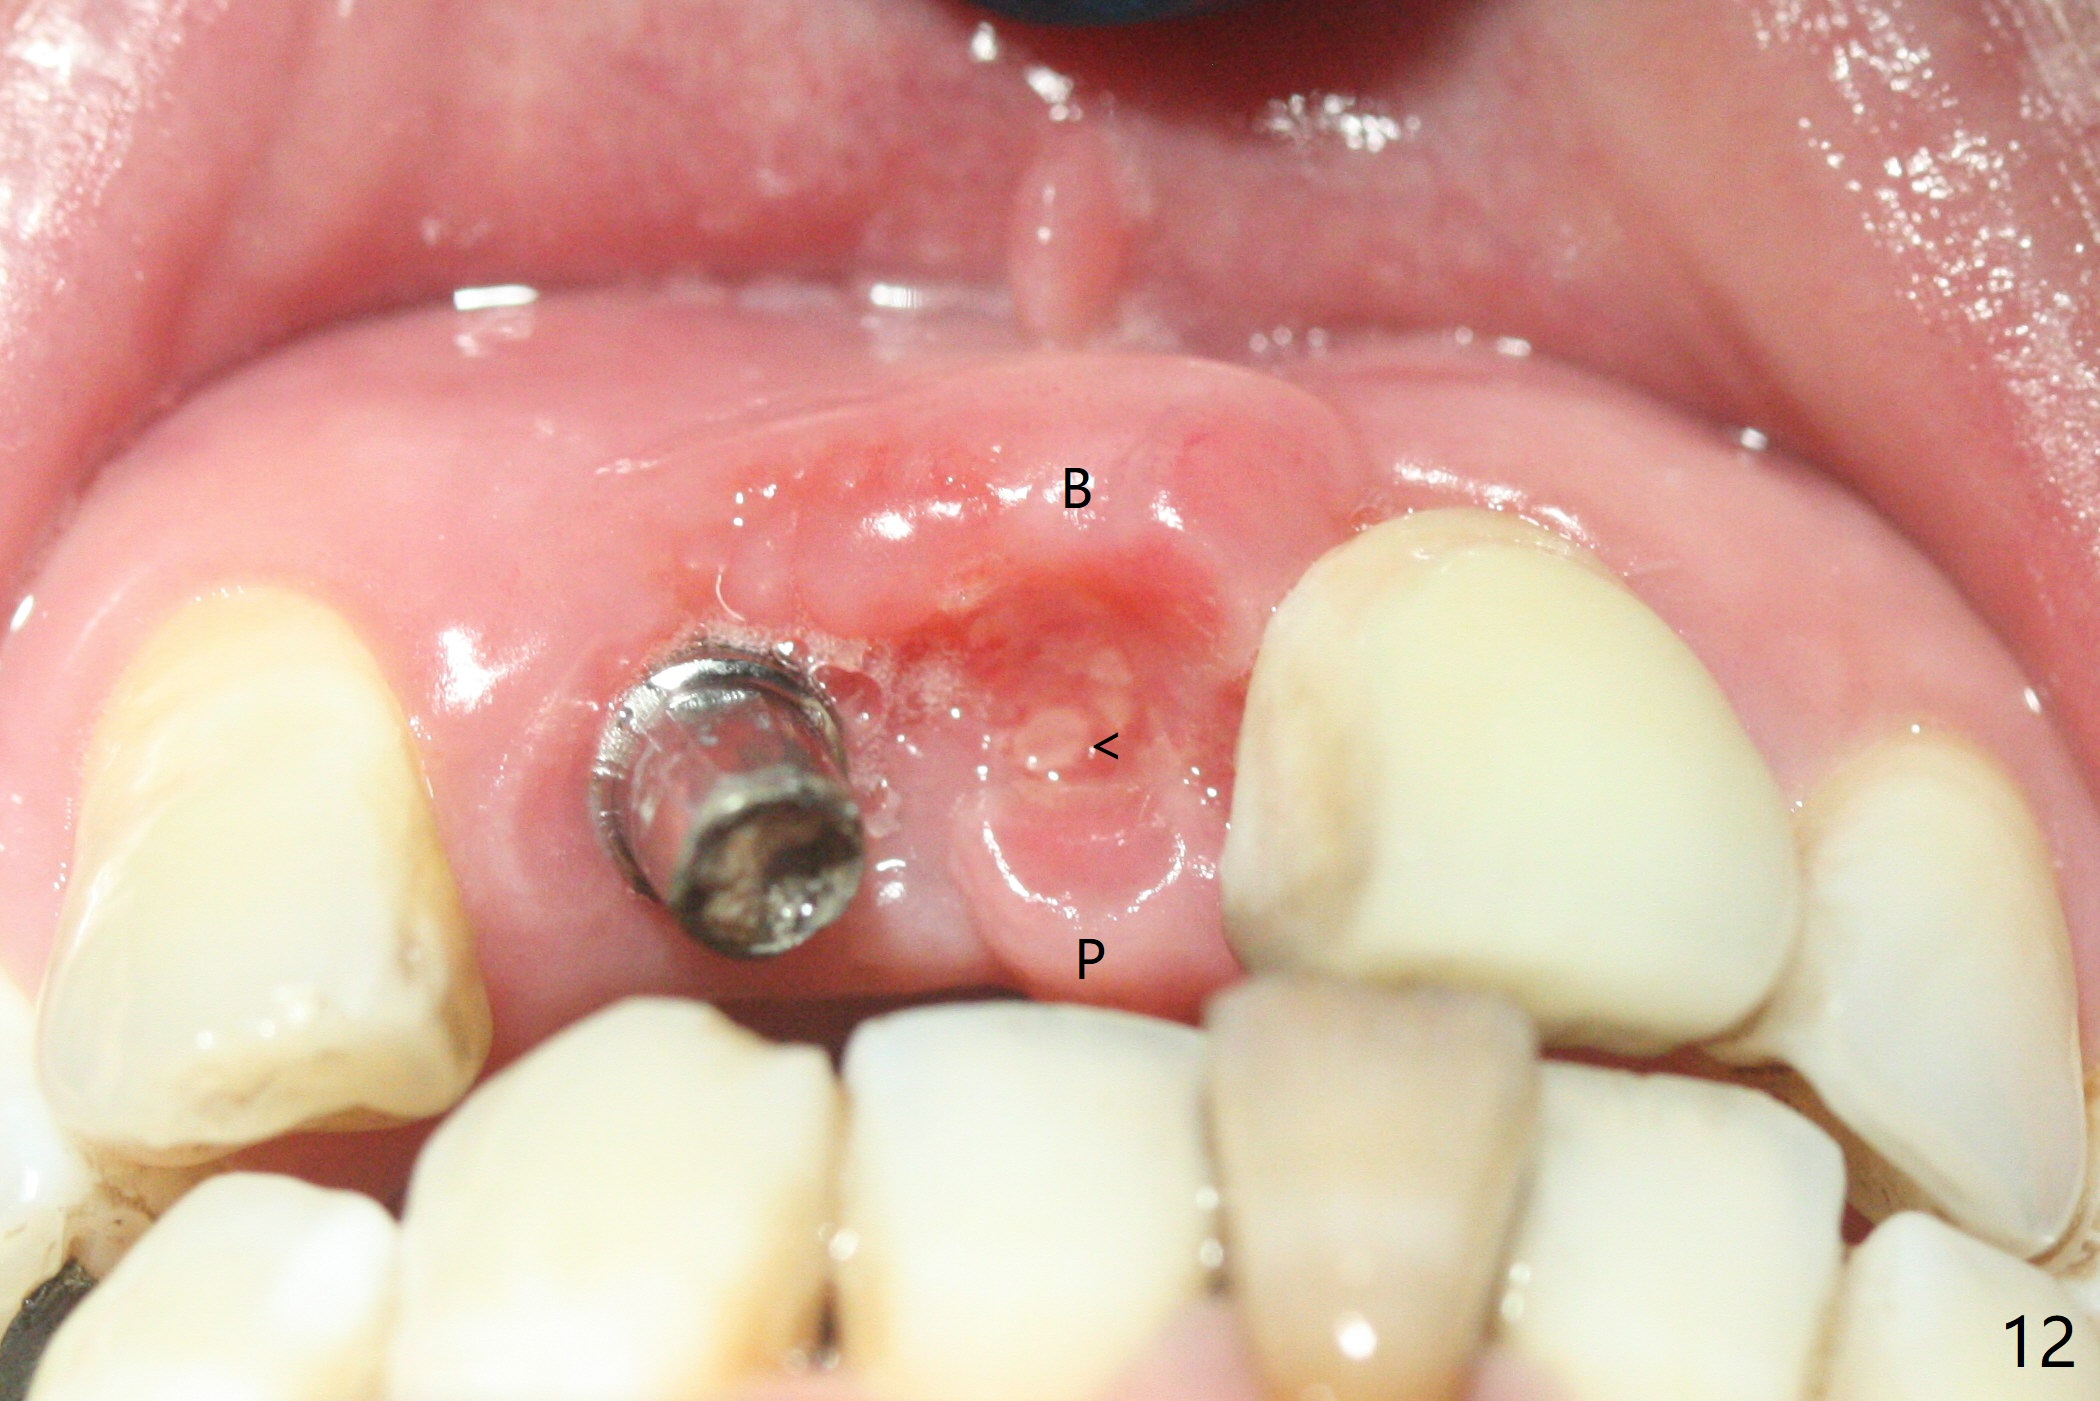

拆除部分桥发现:中,侧切牙牙龈红肿(图一),不利于切口和伤口愈合。不过还是在中切牙区切开,牙龈相当厚,有利于今后牙龈形成凹陷和乳头。坏消息是近远中距离太短,不利于植牙以及今后局部卫生维护,所以决定只在侧切牙种植(图二,三),完成钻洞后,颊侧根尖穿孔植骨,然后植入植体,即刻放置修复基台(图四 (*:牙龈乳头)),暴露基台牙龈缘,制作临时悬臂桥 (图五),两个中切牙牙冠长度差不多,插入临时桥时颊侧牙龈乳头基本形成(图六:*),缝合前颊侧,腭侧牙龈瓣下放置粘性骨块(图七,八:* )和PRF膜(图七:^)。最后使用牙周敷料。但愿术后牙龈炎症消失,形成良好牙龈乳头和pontic concavity。 其实由于口腔卫生习惯,术后十七天颊侧牙龈仍红肿(图九),而腭侧正常。如果口腔卫生改善而红肿依然存在,让实验室制作临时桥。术后一个月颊侧牙龈红肿好些(图十),好像骨粉丢失少许,可能与水枪使用有关。右上1牙冠显得太短(*)。也太肥大,因为右上1切缘太颊侧,与左上1对比(图十一:*)。由于颊侧牙龈(图十二:B)术中推向颊侧,与腭侧(P)牙龈之间放置大量粘性骨粉,术后一个月骨粉(<)形成牙龈,形成凹陷。颊侧萎缩不再明显了。右上1牙冠颈部多加些树脂,牙齿就显得长的多(图十三:箭头)。与侧切牙之间颈部故意留下间隙(*),让牙龈入位(空箭头),形成龈乳头。当右上1临时牙冠切缘(图十四:*)移到腭侧,外形改观不少。下次改善侧切牙唇侧。术后两个月三个星期牙龈红肿好像减轻,牙龈没有进入切牙间隙,干脆用树脂关闭(图十五:> <)。下次减少侧切牙切缘(^),适当增加中切牙长度(上提牙龈)。术后3.5个月植体好像整合,基台完全就位(图十六)。术后3.5个月Pontic凹陷形成,但是1,2之间龈乳头始终无法形成(图十七)。以后类似病例应该多种植一个。此例草率取模,可能需要临时粘固,观察植体近中颊侧所谓瘘道,必要刮治。由于比色不佳,需要实验室颜色更改,病人强化卫生,术后七个月,永久性牙冠粘固前,局部牙龈健康(图十八)。